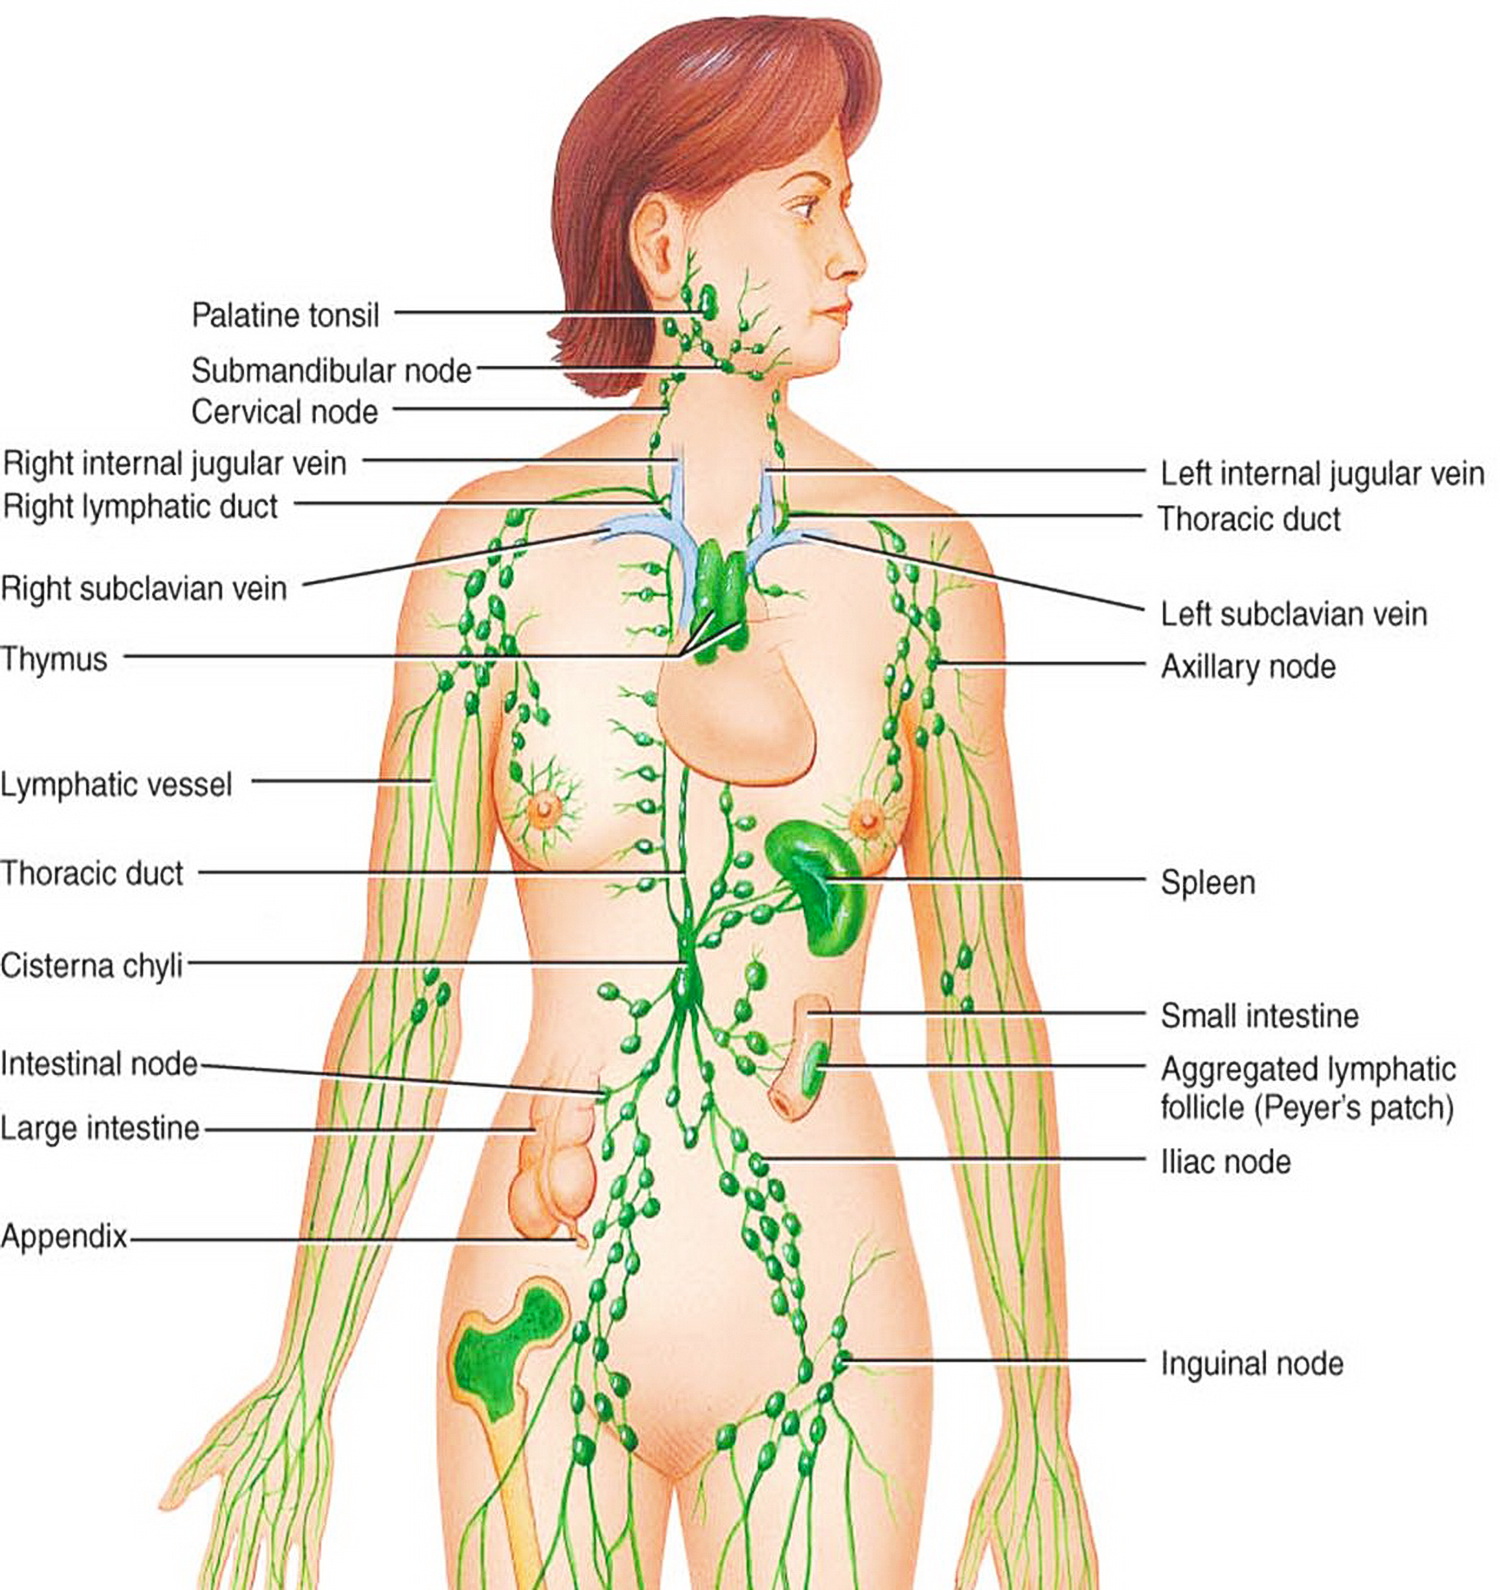

Мезентериальные лимфатические узлы: УЗИ и диагностика